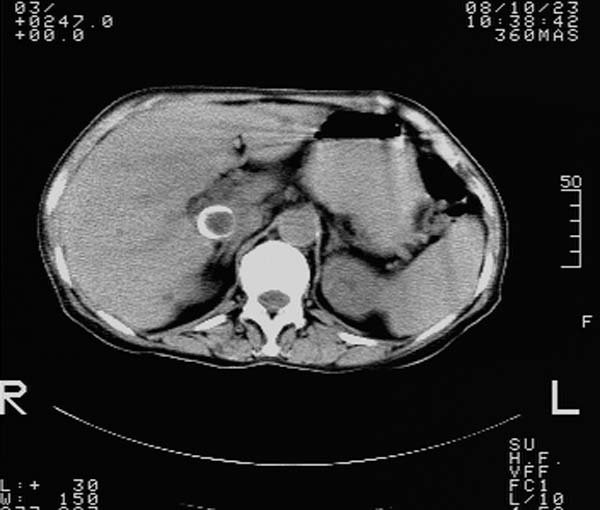

f,67y。反复右上腹痛。余无异常。

前五幅未服造影剂。后面图像有上传重复的。请战友们发表意见。

胆囊结石、胆囊癌伴邻近脏器受侵,不除外黄色肉芽肿性胆囊炎,建议增强扫描。肝多发囊性占位性病变,囊肿或囊性转移。

胆囊结石、胆囊癌伴邻近脏器受侵,肝转移可能

胆囊内结石,胆囊壁不规则增厚,胆囊胃窦区解剖结构欠清晰,楼主提示为少见病,考虑bouveret综合征?黄色肉芽肿性胆囊炎?肝内多发低密度占位,建议增强或b超

bouveret综合征(胆石性十二指肠幽门梗阻)应重点考虑。期待结果!